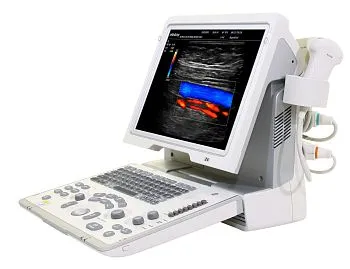

Клинические изображения

Система в большей степени предназначена для общих исследований, но также поддерживает объемные датчики и 3D/4D опции для визуализации плода.

Аппарат подойдет для общих исследований и первичной диагностики, врачей узких специальностей, приемных отделений, а также выездов на дом.